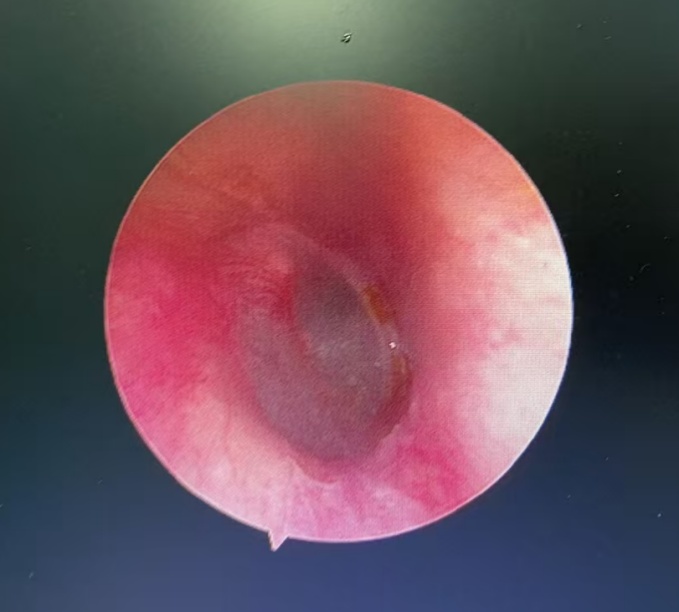

经急诊转诊到耳鼻咽喉头颈外科,医生用电耳镜进行观察,发现一只蟑螂卡在外耳道深处。金先生一直喊疼,并说感觉到耳道内物体的活动。“别怕,我先用石蜡油把虫子杀死,虫子有点深,晚点再通过耳内镜帮你取出来。”医生一边操作一边安抚金先生。

不久后,确认蟑螂已被“处死”,金先生疼痛暂时缓解,大清早又赶紧去做耳内镜,医生最终用镊子从金先生外耳道取出了指甲盖大小的蟑螂,并为他进行耳道消毒。

鼓膜完整

虫子便不会钻进大脑

不仅是蟑螂,连小蚂蚁也能在耳朵里闹出惊天动地的阵势。耳道皮肤非常敏感,且耳道深处紧贴骨头,共振效应明显。患者通常会感到明显的瘙痒感、爬行感。如果蚂蚁爬到鼓膜表面,它的脚步声在患者听起来就像“敲大鼓”或者是巨大的“轰隆”声,令人心烦意乱。幸运的是,只要鼓膜是完整的(没有穿孔病史),虫子就绝对不可能钻进中耳,更不可能钻进大脑或身体其他部位。